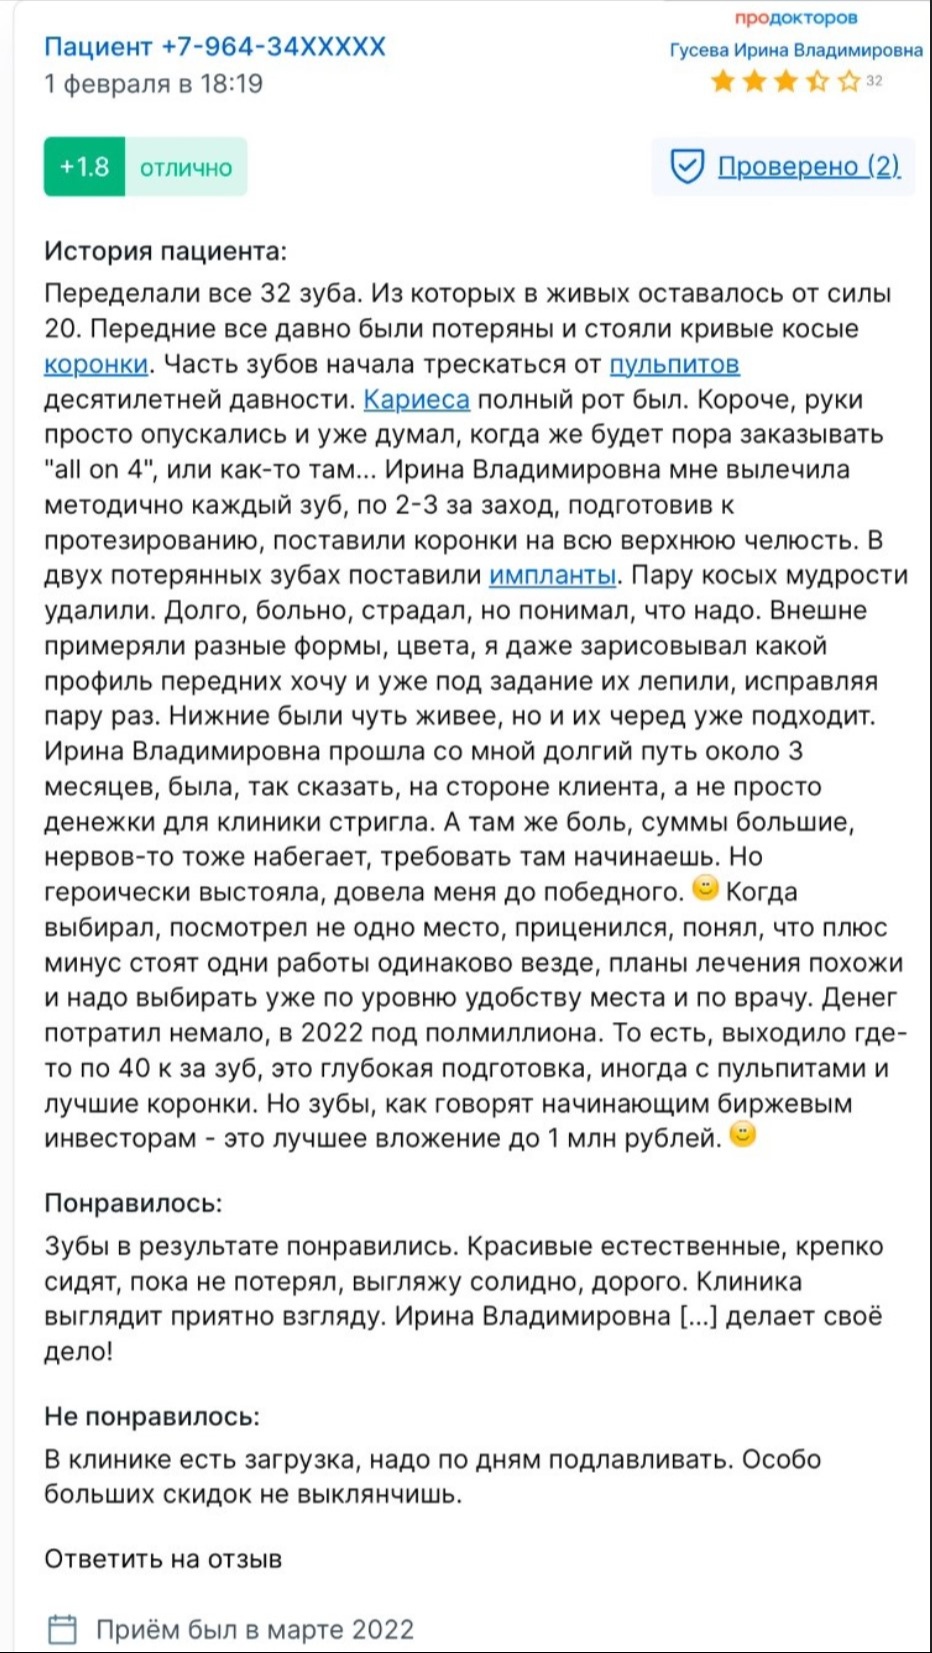

Ирина Гусевастоматолог-терапевт, имплантолог, ортопед

Ирина Гусевастоматолог-терапевт, имплантолог, ортопед